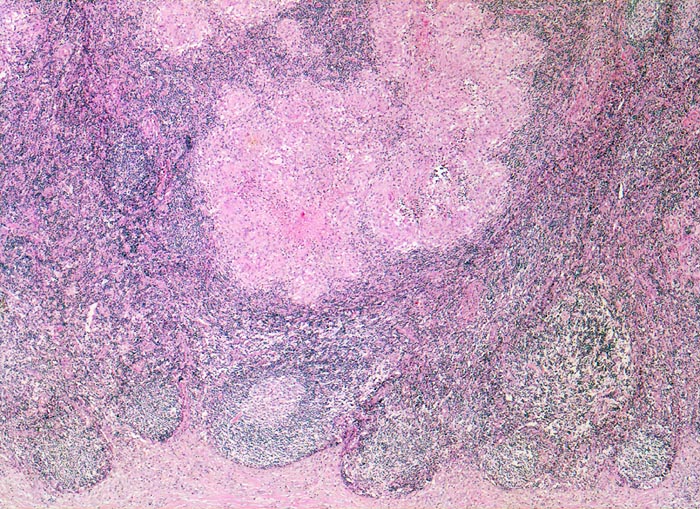

In der mittleren Dermis bilden sich Nekroseareale, welche von palisadierenden Histiozyten, mehrkernigen Riesenzellen und eosinophilen Granulozyten demarkiert werden. Die regionären Lymphknoten zeigen ebenfalls eine retikulozytär abszedierende Entzündung. Diese ist jedoch nicht spezifisch. Sie kommt auch vor bei Yersiniose, atypischer Mykobakteriose, Sporotrichose, Tularämie, Tumoren, Lymphogranuloma venereum und Coccidiomykose.